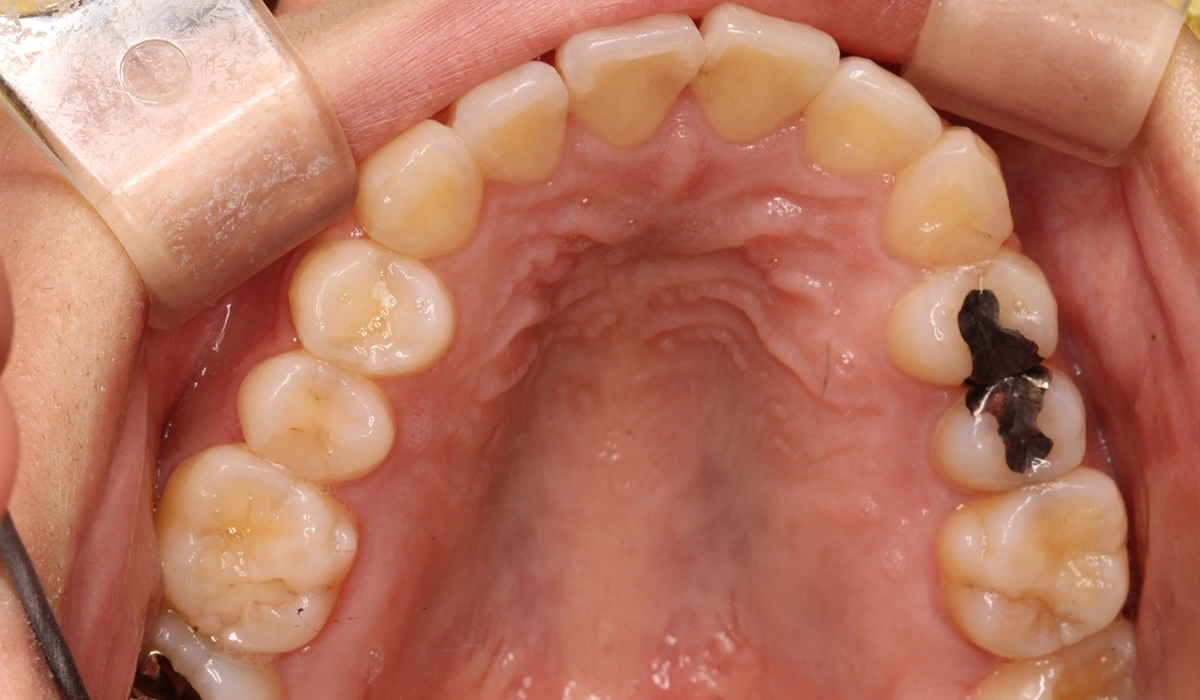

術後:上顎

今回ご紹介する患者様は、上下前歯部のがたつきを気にされており、検査後Ⅰ級叢生と診断いたしました。左上7番予後不良により抜歯し、左上8番を配列したためやや治療期間が長くなるも満足いく配列となり患者様も満足していただけました。

| 治療内容 | 上下前歯部のがたつきを気にされており、検査後Ⅰ級叢生と診断いたしました。左上7番予後不良により抜歯し、左上8番を配列したためやや治療期間が長くなるも満足いく配列となり患者様も満足していただけました。 |